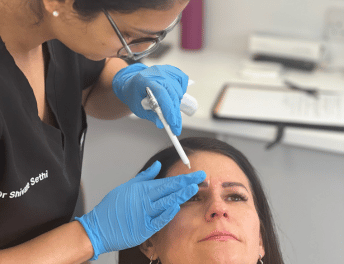

Discover MoreCustom cosmetic solutions to enhance your natural beauty.

Discover MorePersonalised aesthetic solutions for a naturally enhanced appearance.